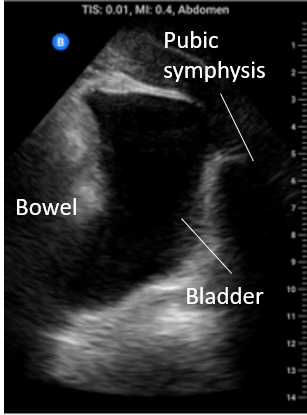

Pelvis: In the midline below the abdominal fold but superior to the pubic symphisis begin with the probe in transverse. Fan posterior to anterior through the bladder. In males pay particular attention to the rectovesical pouch and in females to the rectovaginal space (pouch of Douglas). Also look at the bladder edges for angular anechoic regions indicating fluid settling around the bladder and bowel.

Intraluminal vs extraluminal free fluid: It is important to remember that there are numerous normal abdominal organs that are fluid filled e.g. blood vessels, stomach, gallbladder, and others that can become fluid filled in pathologic states such as small bowel or large bowel in the setting of obstruction. Especially if you are contemplating drainage you need to be certain you are draining abdominal free fluid. As a rule of thumb if fluid forms “corners” and sharp angles, settling into crevices, it is more likely EXTRAluminal and free flowing; see image on the left. If it has round borders it is most likely INTRAluminal or otherwise contained; see the image below on the right, that’s not ascites its a collection that was contiguous with bowel.